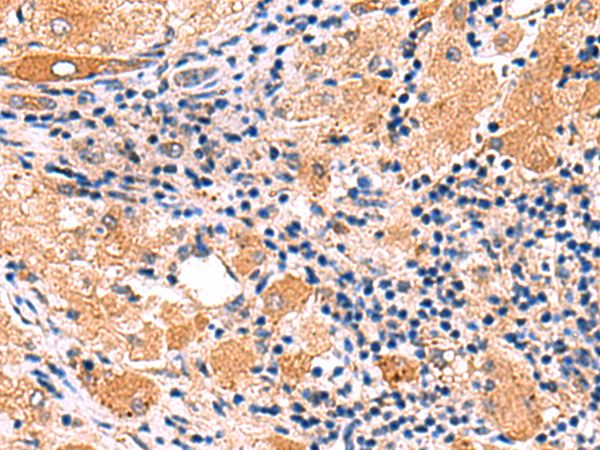

分类: 科研抗体货号: P06789别名:应用: WB,IHC反应种属: Human, Mouse